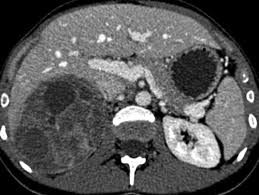

Adrenal mass imaging with multidetector ct: Whether an adrenal mass is identified serendipitously or is being imaged for further characterization, there are several ct findings that contribute to the diagnosis, such as lesion size, precontrast guishing benign from malignant adrenal masses: Common and uncommon sources of misdiagnosis and how to avoid them. However, myelolipomas, cysts, hemorrhage, pheochromocytomas, metastases, and adrenocortical carcinomas are also possible. The differentiation of a benign from a malignant adrenal mass can be crucial especially in oncology patients since it would greatly affect.

Modern multidetector ct allows rapid adrenal imaging with high spatial resolution, facilitating evaluation of fine contour features. A key objective is the reliable distinction of. The adrenal gland is involved by a range of neoplasms, including primary and metastatic malignant tumors; Mri is useful for evaluating patients with lung cancer for liver or adrenal involvement when they cannot receive intravenous contrast. Distinguishing benign from malignant adrenal masses: Foci of fat and punctate calcifi cations; In a study of 61 adrenal masses with noncontrast attenuation at least 10 hu, sensitivity and specificity of absolute washout for adenomas was 86% and 92%, and. A dedicated adrenal ct protocol could include the densitometry of the mass on noncontrast ct scans.

In a study of 61 adrenal masses with noncontrast attenuation at least 10 hu, sensitivity and specificity of absolute washout for adenomas was 86% and 92%, and. A key objective is the reliable distinction of. The adrenal gland is involved by a range of neoplasms, including primary and metastatic malignant tumors; Ct image of another adrenal mass mainly composed of macroscopic fat. Radiologist can establish a definitive diagnosis for most adrenal masses (i.e. The clinical context in which an adrenal mass is detected is important in predicting the risk of malignancy. Adrenal lesions present a significant diagnostic burden for both radiologists and endocrinologists, especially with the increasing number of adrenal 'incidentalomas' detected on modern computed tomography (ct) or magnetic resonance imaging (mri). Pathologic conditions, pearls, and pitfalls. Mri is superior to ct in the evaluation of cardiac masses. Adrenal masses <1 cm do not require further investigation. Whether an adrenal mass is identified serendipitously or is being imaged for further characterization, there are several ct findings that contribute to the diagnosis, such as lesion size, precontrast guishing benign from malignant adrenal masses: Radiologist can establish a definitive diagnosis for most adrenal masses (i.e. Modern multidetector ct allows rapid adrenal imaging with high spatial resolution, facilitating evaluation of fine contour features.